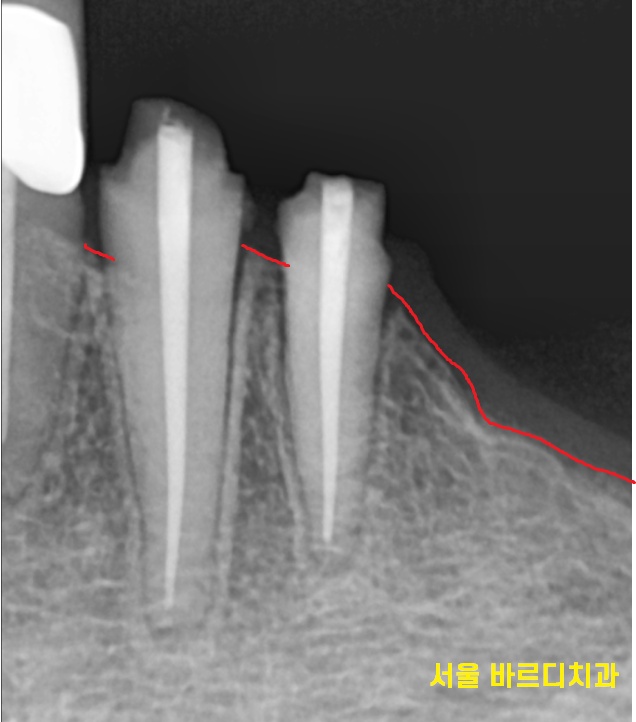

환자분은 뿌리만 남았을 정도로 많이 부러져서

뽑아야했습니다.

뽑아야함을 설명드리고

보험 임플란트 2개를 해야할꺼같다 말씀드렸더니

문제의 치아 깨끗하게 발치한뒤

임플란트 2개를 식립해드렸습니다.